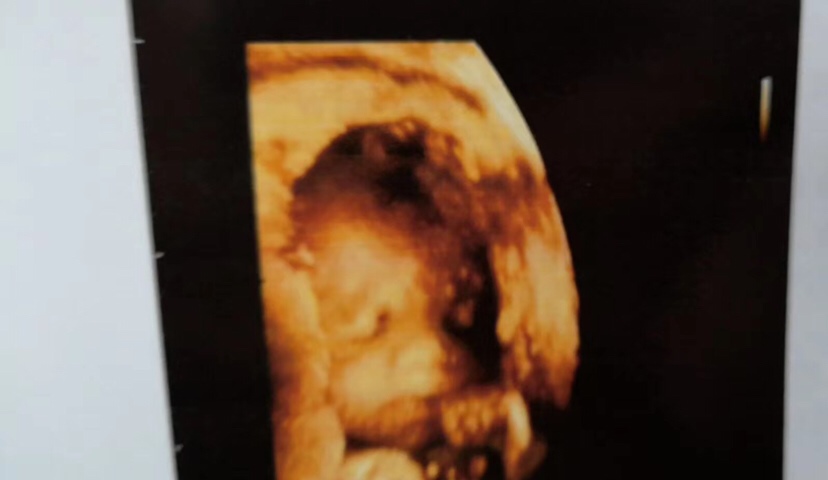

怀孕 孕26周+5天